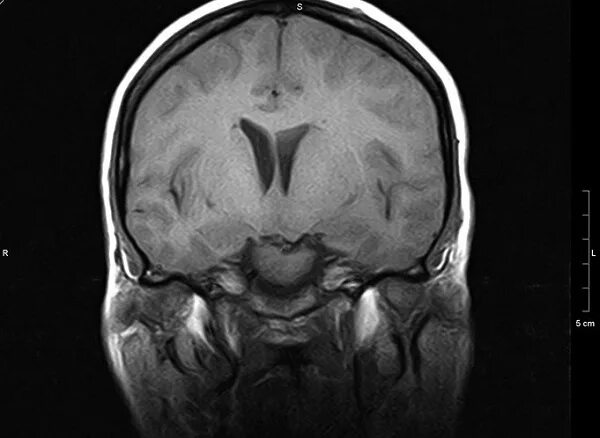

Мрт головного мозга мосто мозжечкового угла